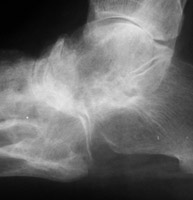

with uniform joint space loss. Bony ankylosis of tarsal bones may occur. In

addition, erosions of the calcaneus may occur at the attachment of the plantar

aponeurosis and/or attachment of Achilles tendon.